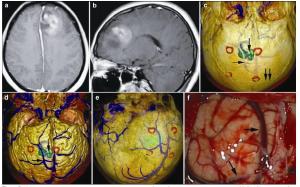

20170308100717  Figure 5 Magnetic resonance imaging, reconstruction images, and actual operative view in a 24-year-old female patient with a glioblastoma in left frontal lobe. (a, b) T1 enhancement scans: The tumor presented as heterogeneous enhancement. (c) 3D reconstruction: 3D reconstruction (skull semitransparent): This picture not only shows the relatioshop between tumor and sutures (vertical double arrow) but also shows the relatioshop between tumor (vertical single arrow) and the superior cerebral veins (horizontal single arrow). (d) 3D reconstruction (do not show the skull): The superior cerebral veins are shown clearly and the tumor (vertical single arrow) is under one large superior cerebral vein (horizontal single arrow). (e) 3D reconstruction (superolateral view, skull, and brian tissue semitransparent): In this picture, we can see tumor, markers, superior cerebral veins, and brain tissue simultaneously. (f) Intraoperative situation: The intraoperative situation is consistent with 3D reconstruction images.